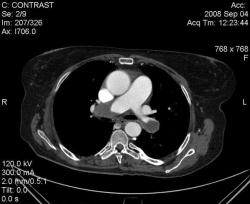

3аключение КТ что: далее цитирую "Патологические изменения в нижней доле правого лёгкого могут соответствовать остаточным явлениям перенесенной пневмонии, инфарктам лёгкого вследствие тромбоэмболии легочной артерии." это не заключение КТ по поводу ТЭЛА. Если пациент изначально направляется на КТ с подозрением на ТЭЛА, то и сьемка должан проводится по протоколу ТЭЛА (срезы 1 мм или ниже; болюс контраст; снимаем снизу вверх против тока крови). Я приведу ниже два скана разных пациентов с ТЭЛА:

скан 1: массивная тромбоэмболия обоих основных стволов.